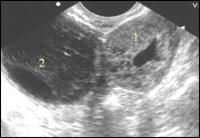

| Рисунок 3

| Эхокартина внематочной беременности Обращает внимание выраженное утолщение стенок трубы (1) вокруг плодовместилища.